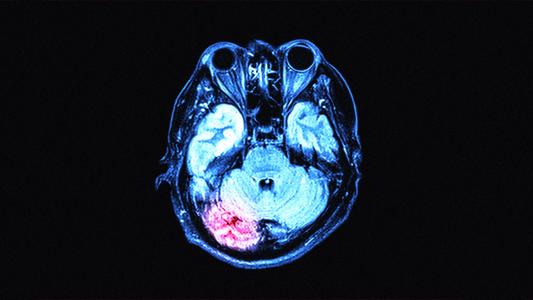

What we know about how the coronavirus affects the brain

Studies are finding that the coronavirus affects the brain as well as the lungs in some patients, causing delirium, strokes, and even fatal swelling.